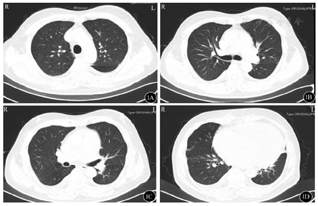

在考虑使用靶向生物制剂之前,我们决定再次对该患者进行多维评估,特别是共病的筛查。完善心肌标志物、心脏彩超、MRI心脏功能(图4,图5)增强扫描并请心内科专家阅片及评估后考虑诊断"扩张型心肌病、心功能Ⅲ级",予以双腔ICD置入术,同时行强心、利尿、抑制心室重构等对症治疗,哮喘方面我们也成功将激素减量至信必可80 µg/4.5 µg 1揿,2次/ d单药吸入治疗。

治疗3个月后患者自觉呼吸困难症状较前明显缓解,日常生活质量得到提高,修正诊断:1.支气管哮喘(急性发作期);2.扩张型心肌病心功能Ⅲ级;3.肺部感染;4.双侧胸腔积液(少量);5.高血压2级中危。复查心肌标志物:肌钙蛋白-T 15.8 ng/L,肌酸激酶同工酶MB质量2.37 ng/ml,肌红蛋白43.17 ng/ml,尿钠素562 pg/ml,复测肺功能提示"FEV1/FVC 85.3%",在使用信必可80 µg/4.5 µg低剂量维持治疗的情况下未再出现哮喘急性发作,ACT评分为24分,达到临床满意控制。